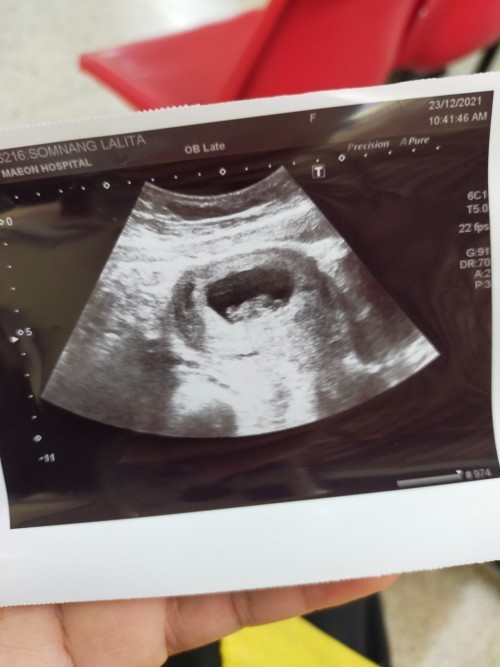

ถุงตั้งครรภ์ 6 สัปดาห์ ซาวไม่เห็นตัวเด็ก เครียดเลยค่ะ

ตั้งครรภ์ 6 สัปดาห์ค่ะ คุณหมอนัดซาวเจอถุงตั้งครรภ์ แต่ยังไม่เห็นตัวเด็ก คุณหมอบอกว่าเห็นถุงไข่แดงข้างใน ตอนนี้แม่เครียดกลัวเปนท้องลม ตอนแม่ๆ6สัปดาห์ ซาวเปนแบบไหนกันบ้างคะ